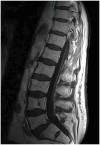

West Nile virus infection poses a significant threat, especially during the warmer months when mosquitoes are abundant. Clinicians must remain vigilant for neuroinvasive illness in patients presenting with febrile symptoms and malaise following mosquito exposure. While magnetic resonance imaging and cerebrospinal fluid analysis aid in differential diagnosis, detecting West Nile immunoglobulin M in serum is crucial for definitive diagnosis. Treatment primarily involves supportive care due to the absence of established regimens, though promising outcomes have been reported with plasma exchange and intravenous immunoglobulin. We present the case of an 83-year-old resident of Alabama, an avid gardener living near a pond, who initially exhibited symptoms of productive cough, diarrhea, fever, and generalized malaise. However, within 48 h, he developed hypoxemia, functional quadriplegia, and bulbar palsy necessitating intubation. Diagnostic evaluations, including magnetic resonance imaging and positive West Nile virus immunoglobulin M in serum, confirmed West Nile virus-associated poliomyelitis viral syndrome, prompting intravenous immunoglobulin therapy. This case highlights the importance of promptly identifying and managing West Nile virus infection, especially in regions susceptible to mosquito-borne diseases, and being vigilant of the disease in non-endemic regions. The case also begs the question of the timing and efficacy of intravenous immunoglobulin and plasma exchange in West Nile virus infection and the fact that more data should be collected on these therapies.

Keywords: West Nile encephalitis; West Nile neuroinvasive disease with poliomyelitis syndrome; West Nile virus; caudal nerve root enhancement; flavivirus.